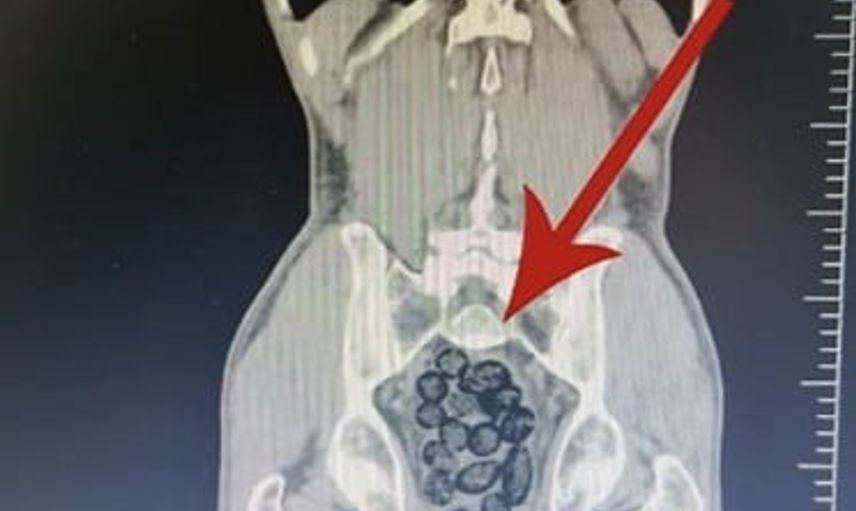

Arama sırasında durumundan şüphelenilen yabancı uyruklu bir yolcu üzerinde yapılan incelemede, şahsın midesinde 64 parça halinde toplam 472 gram metamfetamin bulunduğu belirlendi.

Gözaltına alınan şahsın midesindeki uyuşturucu maddeler çıkartıldı. Emniyetteki işlemlerinin ardından adliyeye sevk edilen zanlı, çıkarıldığı mahkemece tutuklanarak cezaevine gönderildi.